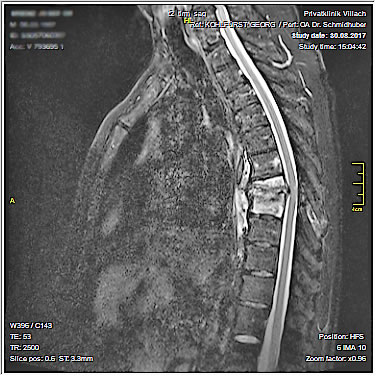

| Leider ist es zum 2. Anlauf nicht mehr gekommen. Schon in Deutschland bekam ich zunehmende Schmerzen im Rückenbereich. Nach der Rückkehr wollte ich eine physikalische Therapie beginnen, aufgrund aber zunehmender Schmerzen und zusätzlich auftretender massiver Kreislaufprobleme musste ich am 14.6.2017 mich für insgesamt 28 Tage in stationäre Behandlung in die Privatklinik Villach begeben. |

Die Spondylodiszitis ist eine Entzündung der Bandscheibe und der beiden angrenzenden Wirbelkörper, die meistens durch bakterielle Infektionen, aber auch entzündliche rheumatische Erkrankungen verursacht wird und die Wirbelkörper auflöst. Die Symptomatik ist zunächst unspezifisch, die Schmerzen entsprechen in Stärke und Ausbreitung denen, die durch degenerative Veränderungen der Wirbelsäule ebenso verursacht werden können. Schmerzen treten vor allem nachts oder bei Belastung auf und sind manchmal begleitet von Nachtschweiß, Fieber oder Gewichtsabnahme. Sehr charakteristisch ist ein starker Klopf- und Druckschmerz der betroffenen Wirbel. Je nach der Schwere des Krankheitsbildes muss die unumgängliche, intensive antibiotische Behandlung unter Umständen durch operative Maßnahmen ergänzt werden. Eine Operation wird vor allem dann nötig, wenn eine kalkulierte Antibiose nicht zur Besserung führt oder neurologische Ausfallerscheinungen auftreten. Das Bandscheibengewebe wird operativ entfernt, die benachbarten Wirbelkörper miteinander verblockt, um jede Bewegung in dem betroffenen Segment zu unterbinden. Zur Sicherung des Erregers und Resistenzbestimmung kann manchmal eine CT-gesteuerte Biopsie angewandt werden.

Die Betroffenen müssen immer, auch bei konservativer Behandlung, eine strenge Bettruhe für 6 bis 8 Wochen einhalten. Zusätzlich wird eine stabilisierende Rumpforthese gegeben. Die notwendige Behandlung und die Überwachung des Verlaufes dauern meistens lange, in der Regel deutlich über ein Jahr. |

| Körperliche Aktivitäten und auch das Reisen war somit im Jahre 2017 nicht mehr möglich. Unser Plan ist, wenn alles klappt, Ende März oder Anfang April 2018 (je nach Wettersituation) in die Thermen nach Ostungarn zu fahren. Das Wohnmobil wurde abgemeldet und steht bis auf weiteres in der Garage. |